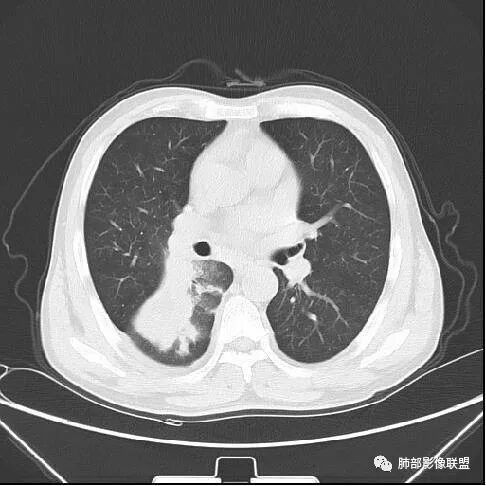

远端确实有膨隆,边缘凹凸不平,换个角度,这个病灶紧贴着斜裂外带。

南边:紧贴着斜裂过来的一个病灶,它的特点是:外围大,内带小。它整个下叶背段体积与对侧相比稍微缩小一点,但是缩小地不是很厉害。外支朝前下走了,仔细看血管,肺动脉走行自然,直达远端。远端实变区是肉芽肿成分,稍微有一点低密度,没有明显坏死,稍微有一点点坏死。而且附近有很多卫星灶,附近很多斑片影,有一些明显有气道壁增厚,细支气管炎的特点,还有就是下叶其他段很多斑片状影。换个角度,第一如果是肺癌,刚才看到PET-CT提示肺癌伴阻塞性肺炎,这个是不符合的。第二如果是肺癌阻塞性肺炎,近端血管肺动脉走行不会那么自然集聚的,这个是不符合的。理由是:如果这个病灶是肺癌,那么明显属于中央型肺癌,中央型肺癌的特点是近端大,远端小,近端是一个肿块,远端阻塞,远端阻塞是阻塞性炎症或者不张,它应该体积缩小,斑片状实变,不会这么密实。刚才有老师提到支气管,这个片有缺陷的地方,给的图像好像那层,如果把其他图像拿开再重叠一下。

南边:这个肺门区,11区和7区都有一些淋巴结,淋巴结的形态不是类圆形,而是梭形的。这个病灶给的图比较少,个人倾向,第一强化非常均匀,肉芽肿性病变;第二,里面血管走行非常自然,远端大近端小,倾向炎性,特别是下面还有斑片状影,非阻塞远端,支气管远端病灶下叶背段,其他段也有,所以我倾向炎性;另外,它里面整个走行符合支气管树爬行征,我倾向结核可能,首先我定在炎性,其次有没有结核的可能。

鉴别诊断:肺炎性肺癌,胸膜下起源,外围大,局部占位效应,有膨隆有收缩,这个不太支持。支气管走行里面没有看到支气管进入很自然堵塞的粘液栓的特点。附近这些磨玻璃影,它的磨玻璃影要么边界清楚,要么由内朝外蔓延的,而不是沿着支气管束蔓延的。而且附近斑片状影,有些似乎有结节感,但是大部分不是,它不是我们常见的磨玻璃样结节,有些有,导致像腺泡样结节那种椭圆的沿着血管束分布的,我会把肺炎型肺癌放在待排。

右肺下叶背断肿块,外围大,内带相对狭长         远端有膨隆,边缘模糊、凹凸不平         血管走形自然,病灶近端支气管通畅,沿支气管树蔓延         周边有多发病灶,多为磨玻璃密度且边界不清。